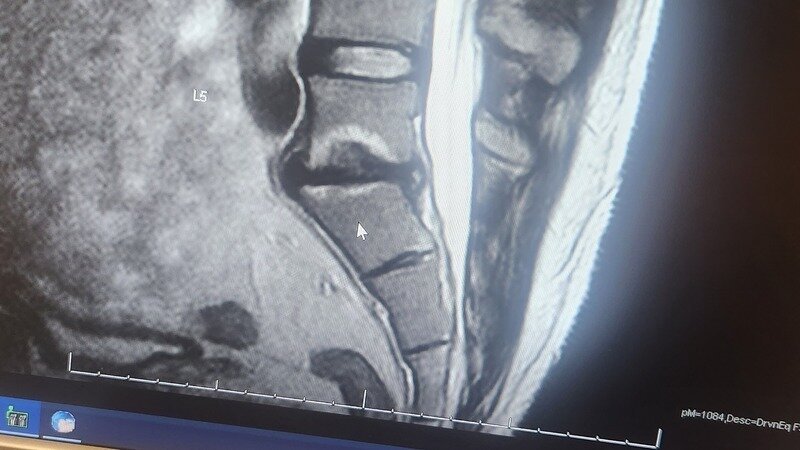

I am a 36-year-old individual suffering from degenerative disc disease. For almost two years, I have been living in constant pain. A potential solution to my agony is the Intracept procedure - a treatment that could give me my life back. However, my insurance provider, Blue Cross and Blue Shield FEHB, has denied coverage for this life-altering procedure.

The Intracept procedure is not considered experimental or exploratory; it's an FDA-approved treatment designed to alleviate chronic low back pain caused by degenerative disc disease. Unlike spinal fusion surgery - which could force me into early retirement and doesn't guarantee a pain-free existence - the Intracept procedure offers hope for a better quality of life.